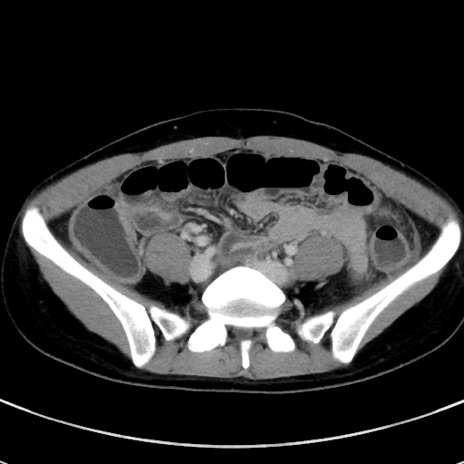

症例17(横断像)

【症例】20歳代女性

【主訴】嘔吐、下腹部痛

【現病歴】昨日夕食後に嘔吐し下腹部痛が出現。本日になっても嘔吐持続し改善しないため来院。

【身体所見】意識清明、BT 37.2℃、BP 108/67mmHg、腹部:平坦、やや硬、下腹部正中から右にかけて圧痛あり、反跳痛軽度あり、tapping pain(+)。

【データ】WBC 13600、CRP 14.94